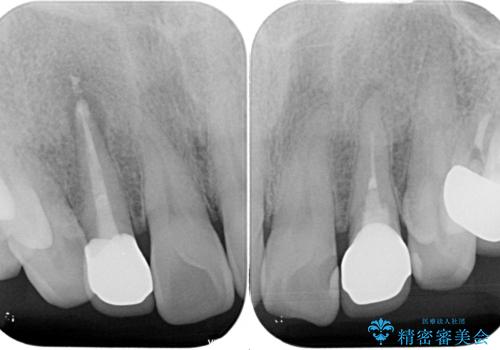

金属の土台を外し、ファイバーコアを築造し、オールセラミッククラウンに適切な形に整えました。

左上の2番目の歯の型どりの段階で患者様より右上の2番目の歯も治療をしてほしいとのことで、根管治療(保険診療)、ファイバーコア、オールセラミッククラウンによる補綴治療を行いました。

歯と歯茎の間に圧排糸と言われる糸を入れてシリコーン印象材にて型どりをしました。